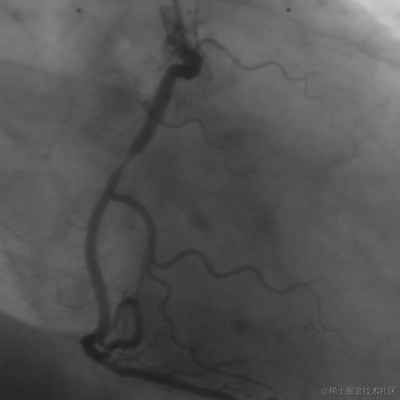

还是以前面的图为例:

7 calculate_lines_gauss_parameters (8, [10,4], Sigma, Low, High)

8 lines_gauss (Image, Lines, Sigma, Low, High, 'dark', 'true', 'parabolic', 'true')

9

10 dev_set_color ('green')

11 dev_display (Image)

12 dev_display (Lines)

复制代码